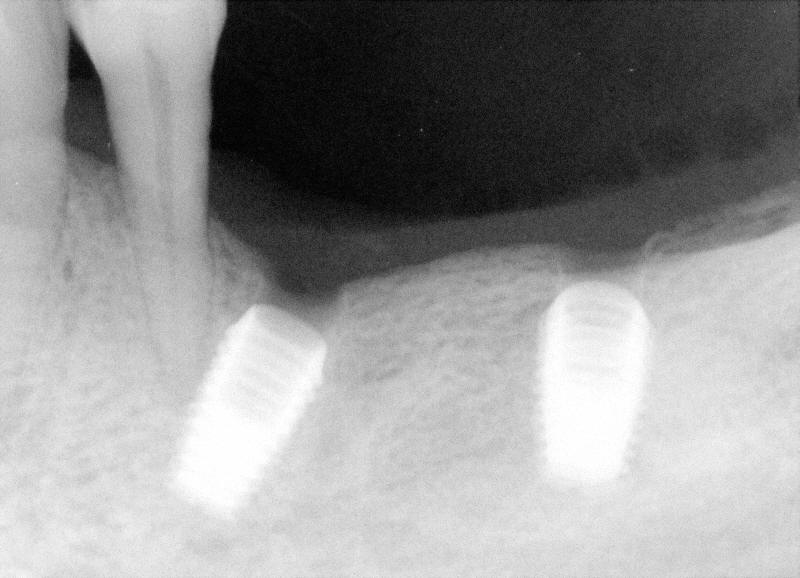

Fig.1 38 year-old male patient presented in 2006 with chief complaint "loose bridges". Exam shows poor oral hygiene and restoration, and advanced periodontal disease. Initial treatment includes removal of grossly nonsalvageables, scaling & root planing, and upper removable partial using #1 as distal abutment. Due to pneumatic sinuses and finance, implants would be placed in the mandible first. | |

Fig.2 High looped mental nerve is noted pre-op. To avoid potential damage to the nerve, local infiltration was used. Flap was raised to expose the mental nerve before osteotomy. A shorter implant was chosen for #29 (5x6mm), as compared to 5x8 implants (Bicon) for #28 and 30. The depth of osteotomy for #29 was controlled so as not to pass below the mental foramen, but still to bury implant platform. According to manufacture manual, the implant should be buried 2-3 mm below the ridge. No paresthesia was found post-op, although #29 implant was apparently on the top of the mental nerve (red tracing line). As shown below by cone-beam, the apex of this implant must be located lingual to the mental nerve when the latter exits the mental foramen. The drawback is that a few of threads was exposed buccally for #29 implant (not shown), probably because it was not buried deep enough. The thread exposure was found during uncovering, 4 months after placement. No further treatment was pursued for thread exposure. Integrated abutment crowns were placed for #28-30. This panorex was taken 1.5 years after crown placement. Radiographically, implant thread is below the alveolar ridge. Twenty eight months since functioning, these 3 implant-supported crowns have been stable with healthy bone and gingiva. | |